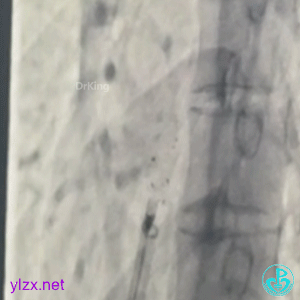

3 手术过程

左盘展开

左盘展开,牵拉成型线,使左盘面成型,后撤鞘管和钢缆,使封堵器左盘贴靠房间隔。

右盘展开

右盘展开,牵拉成型线使封堵器双盘更好的扣合于间隔上。